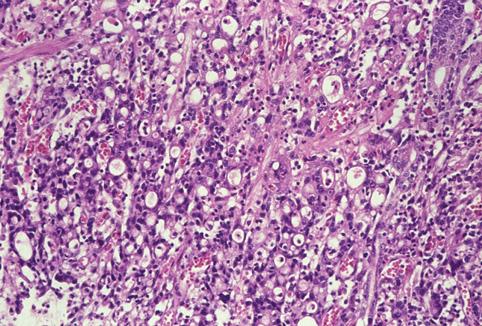

질환(병리주체)의 분류 악성 상피성종양/선암

부위(장기별) 위(부위)/체부

검사방법 마이크로

종양의 육안분류 0형(표재형)/III형(III+IIc)

종양의 최대경(밀리미터) 20~24

종양의 심달도 m